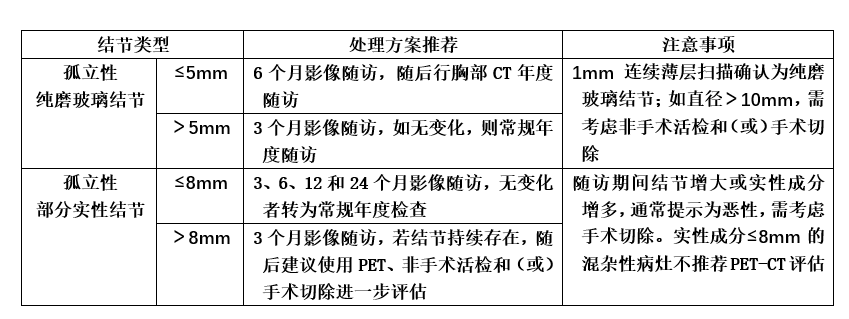

孤立亚实性肺结节的随访

孤立亚实性肺结节包括部分实性结节(mGGN)和纯磨玻璃结节(pGGN)。

☞ 部分实性肺结节的随访:≤8mm者,建议在3、12、24个月进行CT复查,无变化者转为常规年度检查;>8mm者,建议3个月影像随访,若结节持续存在,建议PET-CT、活检或手术切除。需要重视的是,如果部分实性结节增大或实性成分增多,通常提示为恶性,需考虑手术切除。

☞ 纯磨玻璃肺结节的随访:一般以5mm大小为界进行分类观察。直径≤5mm者,6个月复查,随后每年胸部CT随访;直径>5mm者,3个月复查,随后每年胸部CT随访。若纯磨玻璃肺结节>10mm,需非手术活检和(或)手术切除。如定期随访中纯磨玻璃结节增大(尤其是>10mm),或出现实性成分增加,要引起我们高度警惕,常预示为恶性转化,需进行非手术活检或切除。

图三:亚实性肺结节的临床管理流程